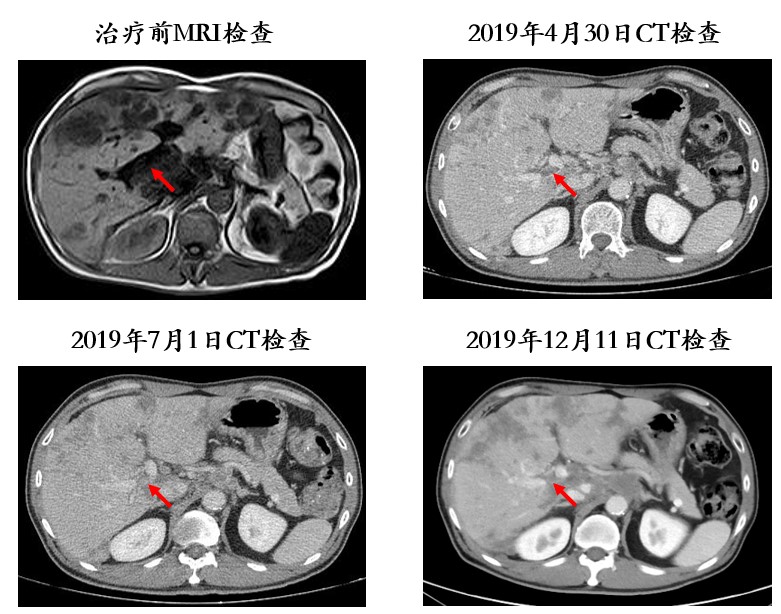

患者男性,51岁,因“上腹隐痛不适3月余,加重1月”于2019年2月23 日入院。既往 “糖尿病”史2年,现血糖控制尚可;饮酒史20余年,每周3~4次,半斤/次;吸烟史:20支/天×20余年。体格检查:皮肤巩膜无黄染,前胸可见数颗蜘蛛痣,心肺查体无阳性体征;右肋沿下3cm可及肿大肝脏,未及腹部包块。实验室检查:癌胚抗原(CEA)6.60 ng/ml,甲胎蛋白(AFP)2.20 ng/ml,HBsAg (-),HBsAb (+),HBeAg (-),HBeAb (-),HBcAb (+),Anti-HCV (-)。入院时肝脏MRI检查示:肝内多发占位性病变,大小不一,T1WI病变呈低信号,T2WI病变呈高信号,内部信号不均匀;门静脉右支见充盈缺损,考虑癌栓(图1)。2019年2月26日行右肝肿物穿刺活检术,病理示“倾向低分化肝细胞癌”。初步诊断:肝细胞性肝癌Ⅲa期,BCLC C期;门脉右支癌栓(Vp3型,程氏Ⅱ型);肝功能Child-pugh A级。

图1. 2019年2月23日入院时MRI检查